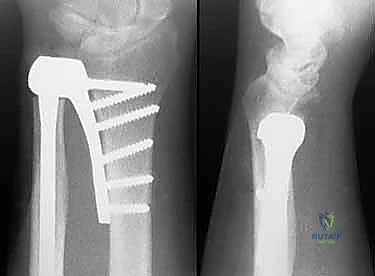

2. التصوير بالأشعة السينية (X-rays)

تُعد الأشعة السينية الخطوة الأولى والأساسية. توضح التآكل الغضروفي، وتكّون النتوءات العظمية، والتغيرات في محاذاة العظام. يقوم الدكتور هطيف بطلب صور في وضعيات محددة (أثناء الكب والاستلقاء) لتقييم الديناميكية الحركية.

5. زراعة المفصل النهائي

بعد تحديد الحجم المثالي، يتم إدخال المفصل الصناعي النهائي. تتكون معظم المفاصل الحديثة من جذع معدني (غالبًا من التيتانيوم) ورأس أملس (قد يكون معدنيًا أو من السيراميك أو البايروكربون). يتم تثبيت الجذع داخل العظم إما بالضغط (Press-fit) أو باستخدام الأسمنت العظمي، حسب جودة عظام المريض.

أنواع المفاصل الصناعية لرأس الزند

تطورت تكنولوجيا المفاصل الصناعية بشكل كبير. يختار الأستاذ الدكتور محمد هطيف أفضل المواد المعتمدة عالميًا لضمان ديمومة المفصل:

- المفاصل المعدنية (Titanium / Cobalt-Chrome): توفر قوة تحمل عالية ومقاومة للتآكل.

- مفاصل البايروكربون (Pyrocarbon): مادة متطورة لها خصائص مرونة مشابهة للعظم الطبيعي، مما يقلل من تآكل عظم الكعبرة المقابل ويوفر حركة سلسة للغاية.

- المفاصل المعيارية (Modular Implants): تسمح بتركيب أحجام مختلفة من الرأس والجذع لتناسب تشريح كل مريض بدقة متناهية.